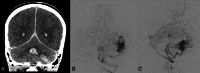

Background: Hereditary hemorrhagic telangiectasia is an autosomal dominant vascular dysplasia characterized by mucocutaneous telangiectasias, recurrent epistaxis, and organ vascular malformations including in the brain, which occur in about 10% of patients. These brain vascular malformations include high-flow AVMs and AVFs as well as low-flow capillary malformations. High-flow lesions can rupture, causing neurologic morbidity and mortality.

Analysis: In this article, a multidisciplinary group of experts on hereditary hemorrhagic telangiectasia reviewed data that support screening guidelines and counter arguments against screening. Children with hereditary hemorrhagic telangiectasia have a preponderance of high-flow lesions including AVFs, which have the highest rupture risk. The rupture risk among children is estimated at about 0.7% per lesion per year and is additive across lesions and during a lifetime. ARUBA, an adult clinical trial of expectant medical management versus treatment of unruptured brain AVMs, favored medical management at 5 years but is not applicable to pediatric patients with hereditary hemorrhagic telangiectasia given the life expectancy of a child. Additionally, interventional, radiosurgical, and surgical techniques have improved with time. Experienced neurovascular experts can prospectively determine the best treatment for each child on the basis of local resources. The "watch and wait" approach to imaging means that children with brain vascular malformations will not be identified until a potentially life-threatening and deficit-producing intracerebral hemorrhage occurs. This expert group does not deem this to be an acceptable trade-off.